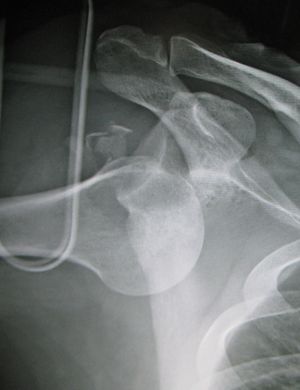

خلع أمامي للكتف الأيسر.

عادة ما يحدث خلع الكتف نتيجة لسقوط الشخص على ذراعه وهي ممدودة أو سقوطه على الكتف.[4] عادة ما يعتمد التشخيص على العلامات الظاهرة على الحالة ويتم التأكد عن طريق التصوير بأشعة إكس.[2] تصنف حالات خلع الكتف إلى خلع أمامي، خلفي، سفلي، وعلوي والأكثر شيوعاً هو خلع الكتف الأمامي.[2][1]

عادة ما يتم تشخيص خلع الكتف اعتماداً على التاريخ المرضي والفحص السريري لها. يتم عمل تصوير إشعاعي لتأكيد التشخيص. معظم حالات خلع الكتف التي تظهر في التصوير الإشعاعي تظهر اختلال في المفصل الحقاني العضدي. قد يكون من الصعب التحقق من انخلاع المفصل الخارجي عن طريق التصوير الإشعاعي الاعتيادي، لكن يتم اكتشافها بسهول عن طريق أعراض تشخيصية أخرى. بعد رد الكتف، عادة ما يكرر التصوير الإشعاعي مرة أخرى للتأكد من نجاح الرد وللوقوف على إصابات العظام. عند تكرار خلع الكتف، يستخدم التصوير بالرنين المغناطيسي لتقييم الأضرار التي لحقت بالأنسجة الناعمة. فيما يتعلق بتكرار خلع الكتف، يعتبر اختبار الترقب (عدم الاستقرار الداخلي) وعلامة سولكوس (عدم الاستقرار الخارجي) من الوسائل المفيدة للوقوف على استعداد الحالة للإصابة بخلع الكتف مستقبلياً.